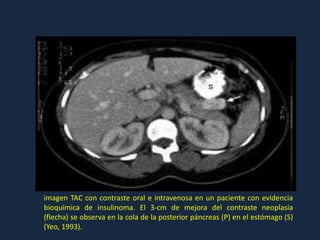

ESTUDIOS DE IMÁGENES

Siempre iniciar estudios de imágenes sólo después de que el diagnóstico ha sido

confirmado bioquímicamente, el 80% de los insulinomas son menos de 2 cm de

tamaño y puede no ser visible por tomografía computarizada o a una ecografía

abdominal.

La localización del tumor preoperatoria éxito se logra en aproximadamente el 60%

de los pacientes ,con la exploración quirúrgica y la ecografía intraoperatoria se

identifican más del 90% de los tumores.

TC helicoidal o multicorte tiene una sensibilidad 82-94%.La En CT helicoidal de

doble fase res más sensible que la de una sola fase para la detección de insulinoma.

RM con gadolinio puede ser útil en la detección de un tumor en el 85% de los casos.

imagen TAC con contraste oral e intravenosa en un paciente con evidencia

bioquímica de insulinoma. El 3-cm de mejora del contraste neoplasia

(flecha) se observa en la cola de la posterior páncreas (P) en el estómago (S)

(Yeo, 1993).